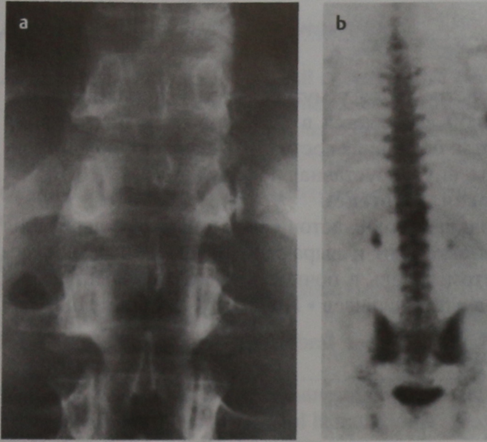

Боль в ночное время. Незначительный сколиоз. Боли устраняются приемом салицилатов. Рентгенограмма пояснично-грудного отдела позвоночника, прямая проекция (фрагмент; а). Выраженный остеосклероз в правой ножке позвонка ТЬХII. Сцинтиграфия костей, прямая проекция (Ь). Повышенное накопление изотопа в правых отделах позвонка Thxll.